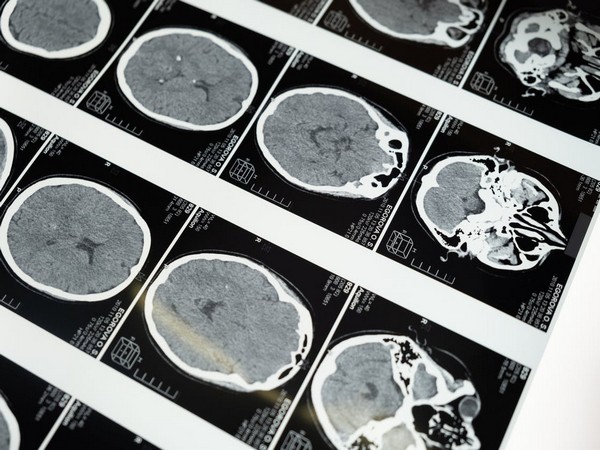

Study shows machine learning can predict development of brain tumours

21 Jan 2023 11:04 PM ISTThe researchers used a deep learning model to turn the MRI data into patient-specific parameter estimates that inform a predictive model for GBM...